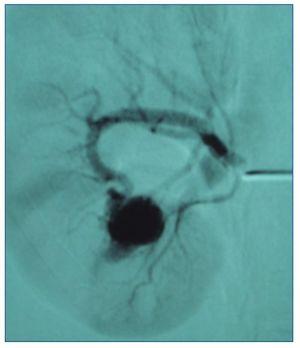

Figura 1. Imagen seudoaneurismática de 2 cm, con importante fístula arteriovenosa asociada.

Se trata de una mujer de 59 años, con antecedentes de hipercolesterolemia y artrosis, que se remite a las consultas de nefrología para estudio de microhematuria persistente y asintomática, sin proteinuria, y función renal normal. Se realiza ecografía renal que muestra riñones de medida y morfología normales. En el seno del riñón derecho se aprecia una imagen hipoecogénica de 17 mm, que en el estudio Doppler se llena completamente de flujo sanguíneo, lo que sugiere la presencia de una MAV. Posteriormente, se realiza una angio-TC, que muestra ambas arterias de morfología y calibre conservados. Destaca la presencia de una lesión hipercaptante de 17 × 22 mm de diámetro en el seno del riñón derecho, con llegada de vasos arteriales y opacificación precoz de la vena renal, lo que indica la existencia de shunt arteriovenoso. Se practica arteriografía no selectiva y selectiva renal derecha por abordaje femoral. Se identifica una imagen seudoaneurismática de 2 cm localizada intrarrenalmente en el polo inferior, con importante FAV asociada (fig. 1). Se procede a estudio supraselectivo intrarrenal, que identifica el pedículo aferente único. Se emboliza selectivamente con microcoils de 4/4 y 3/3 mm, con excelente resultado morfológico final: oclusión del seudoaneurisma, desaparición de la FAV asociada y preservación de la práctica totalidad del parénquima (fig. 2). Tras más de 5 años de dicho procedimiento angiorradiológico, la paciente permanece asintomática y con controles ecográficos sin evidencia de nuevas alteraciones morfológicas.